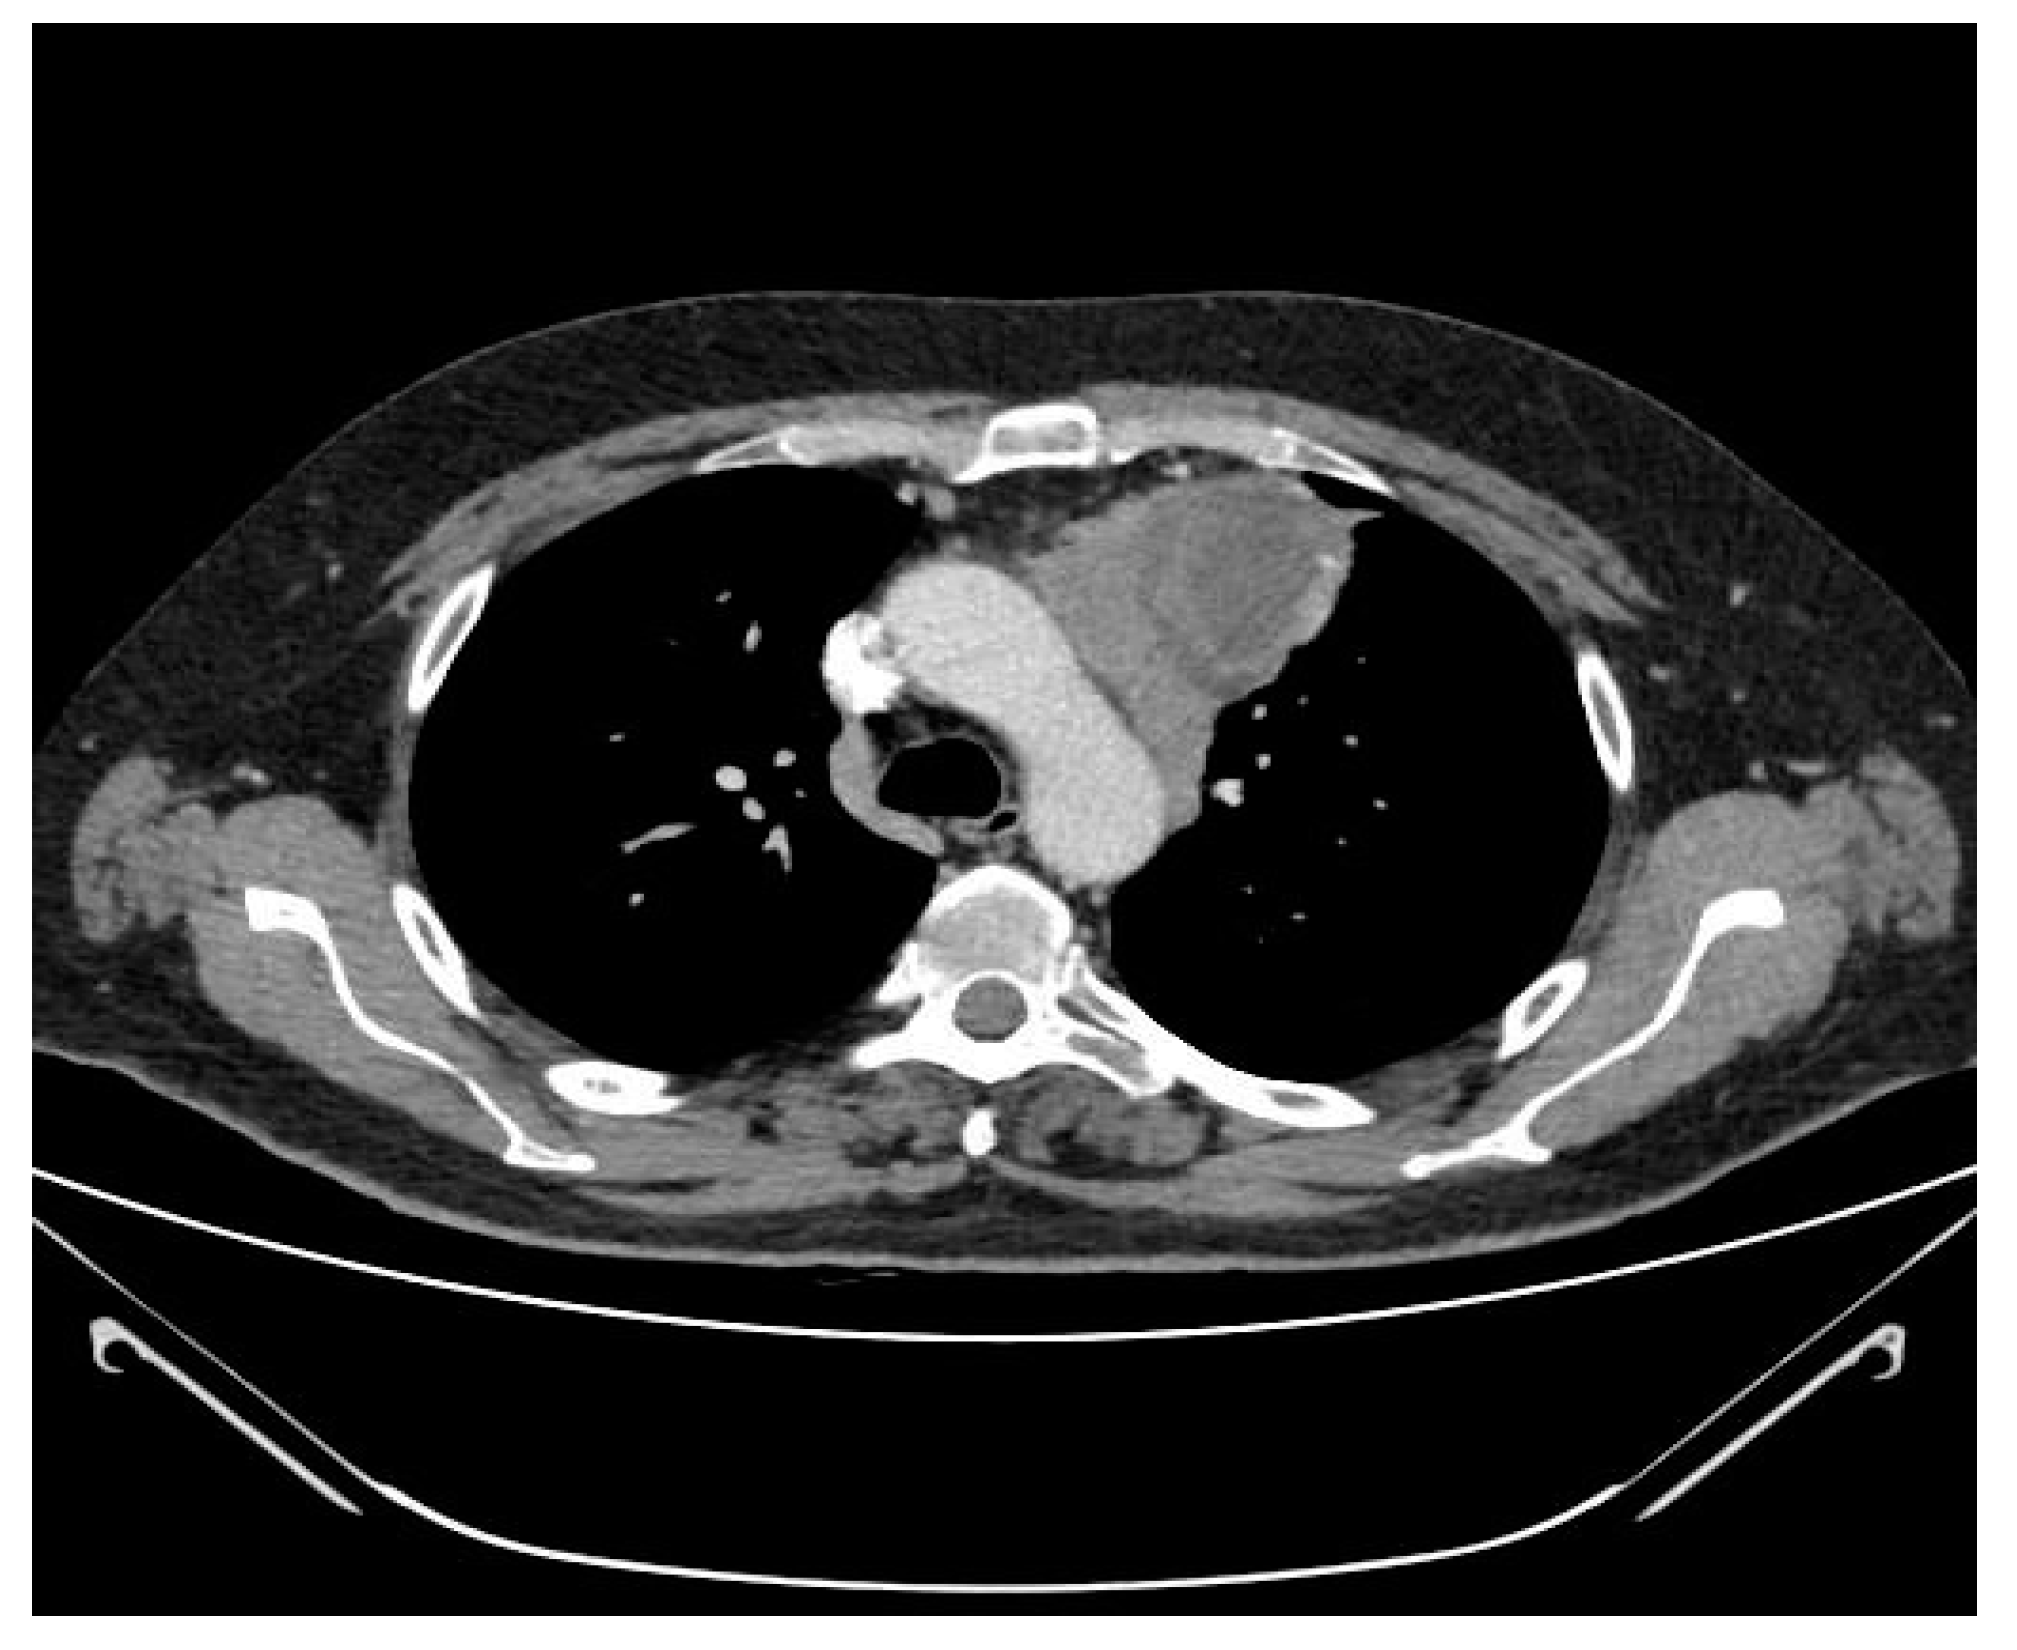

2.3. CT Scan Features and Image Interpretation

3.3. Correlation of CT Scan Parameters, Histology and Staging